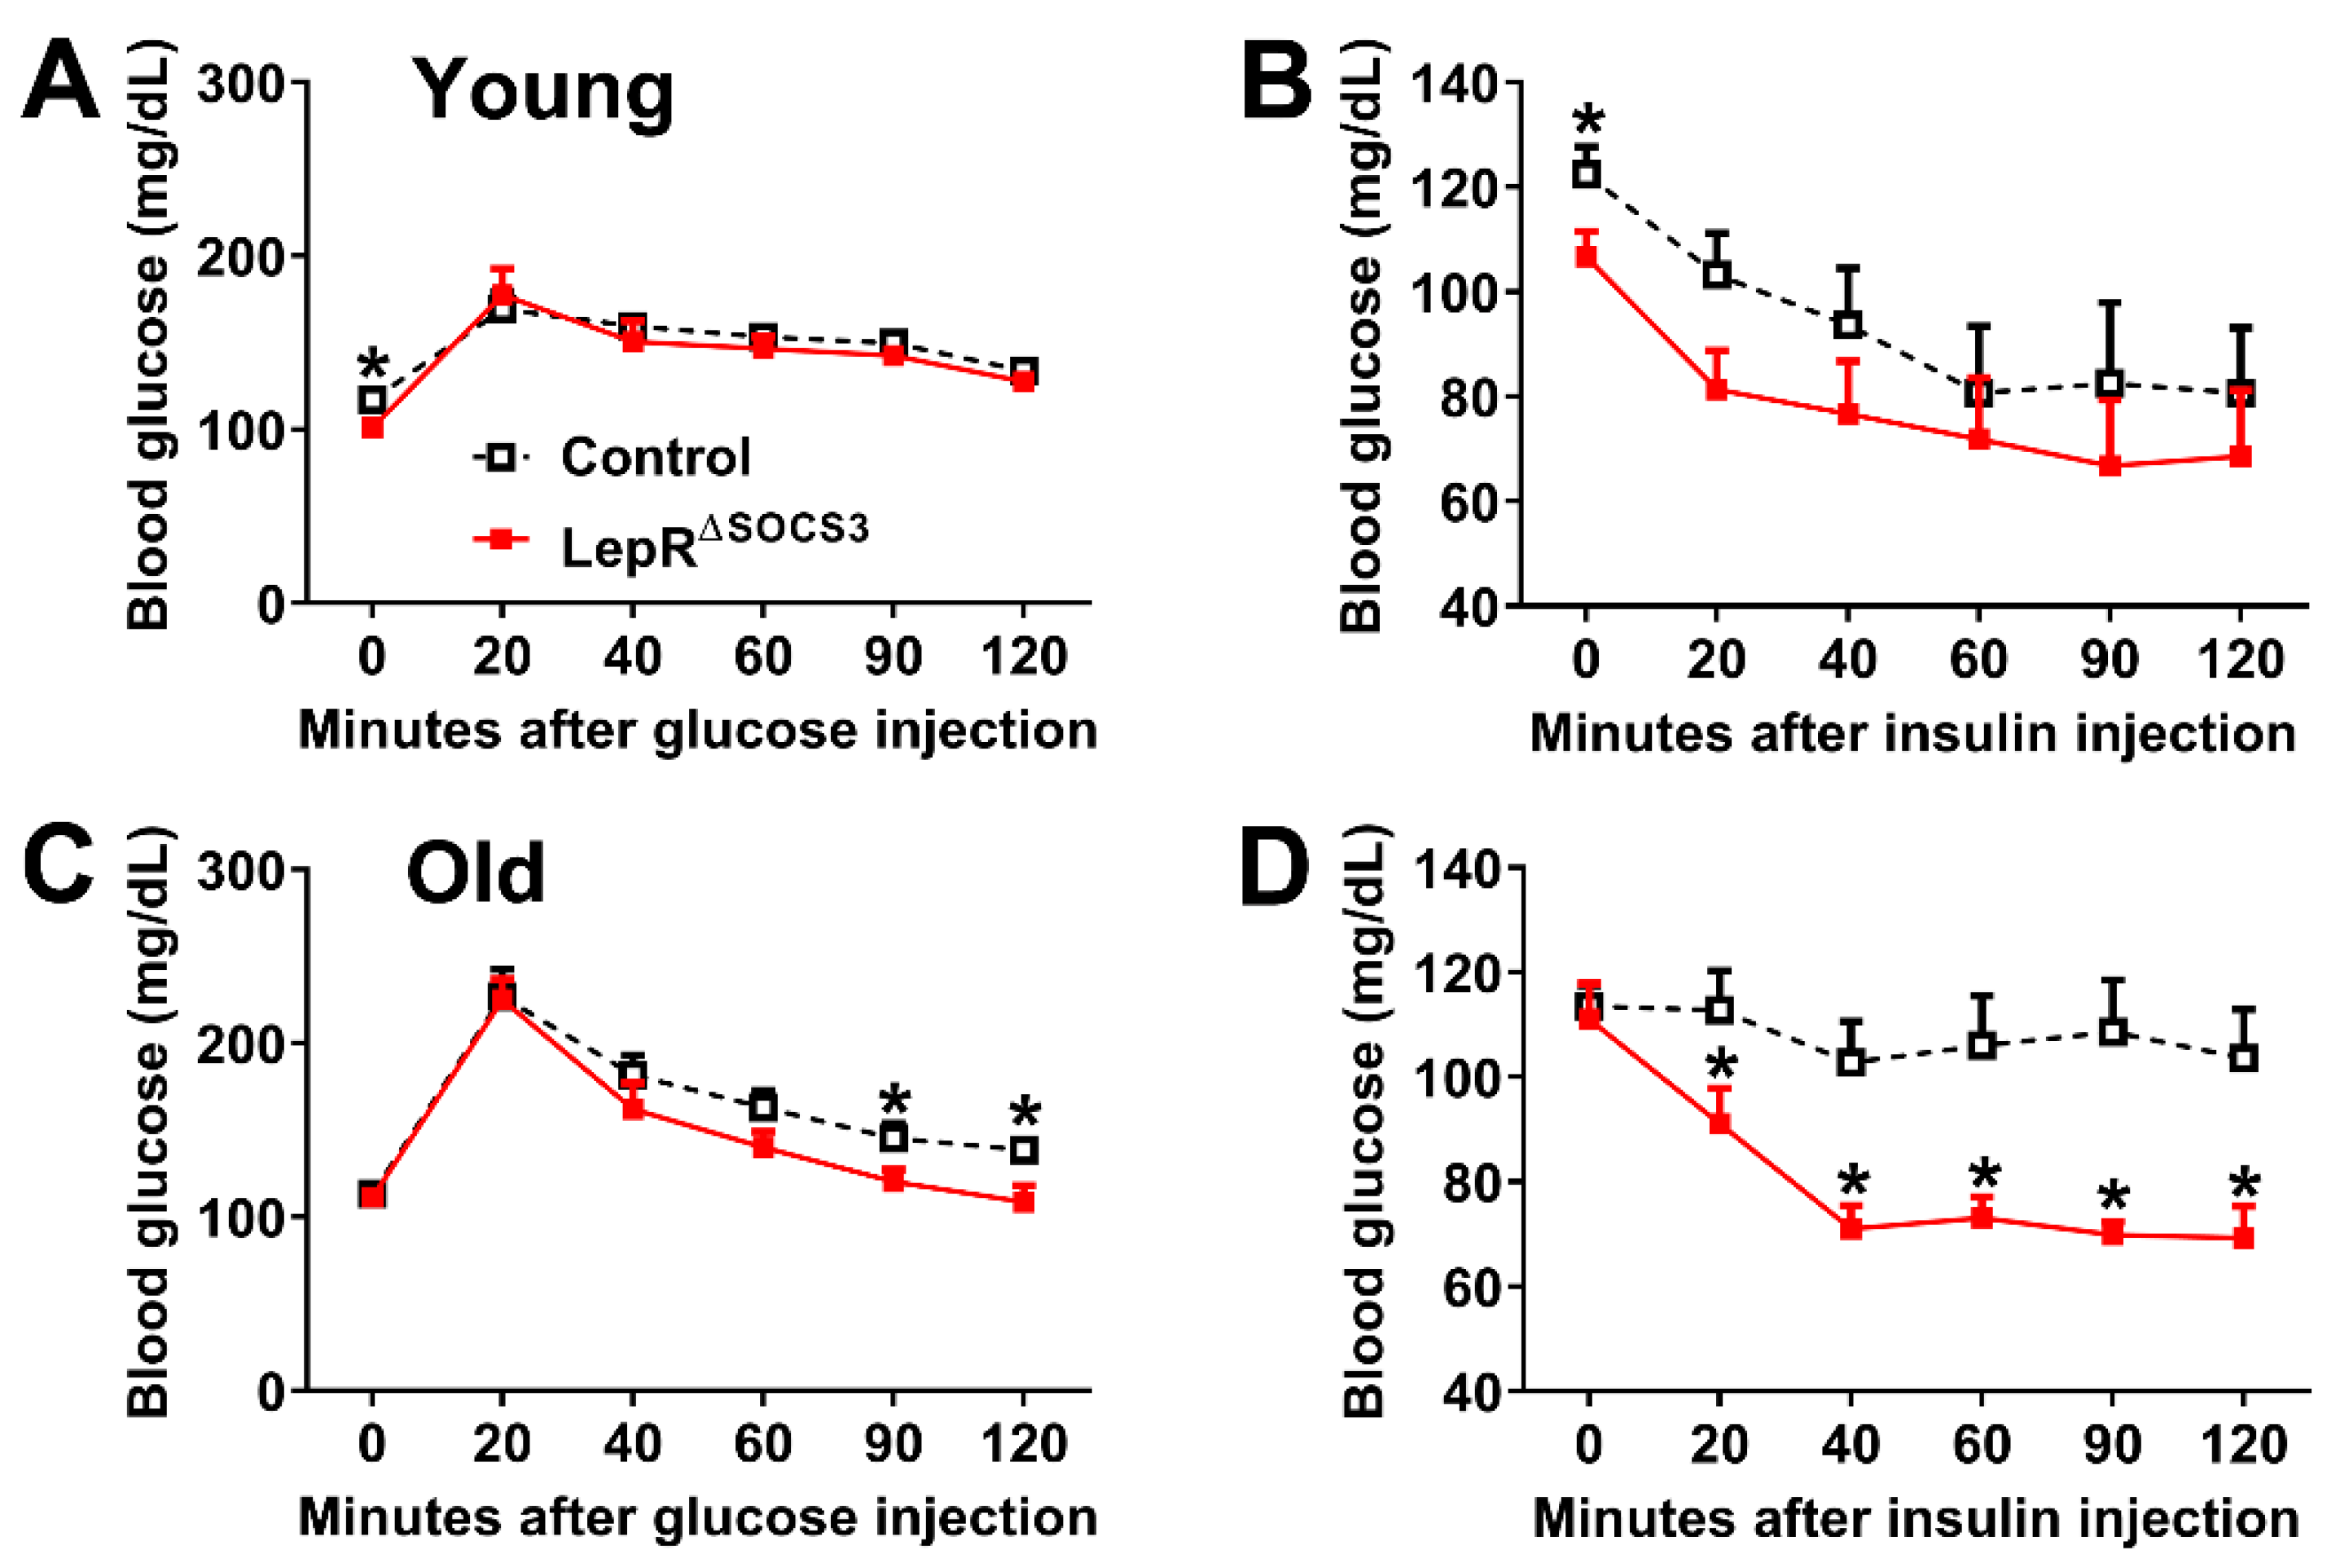

2.1. SOCS3 Ablation in LepR-Expressing Cells Improves Energy and Glucose Homeostasis in Aging Mice